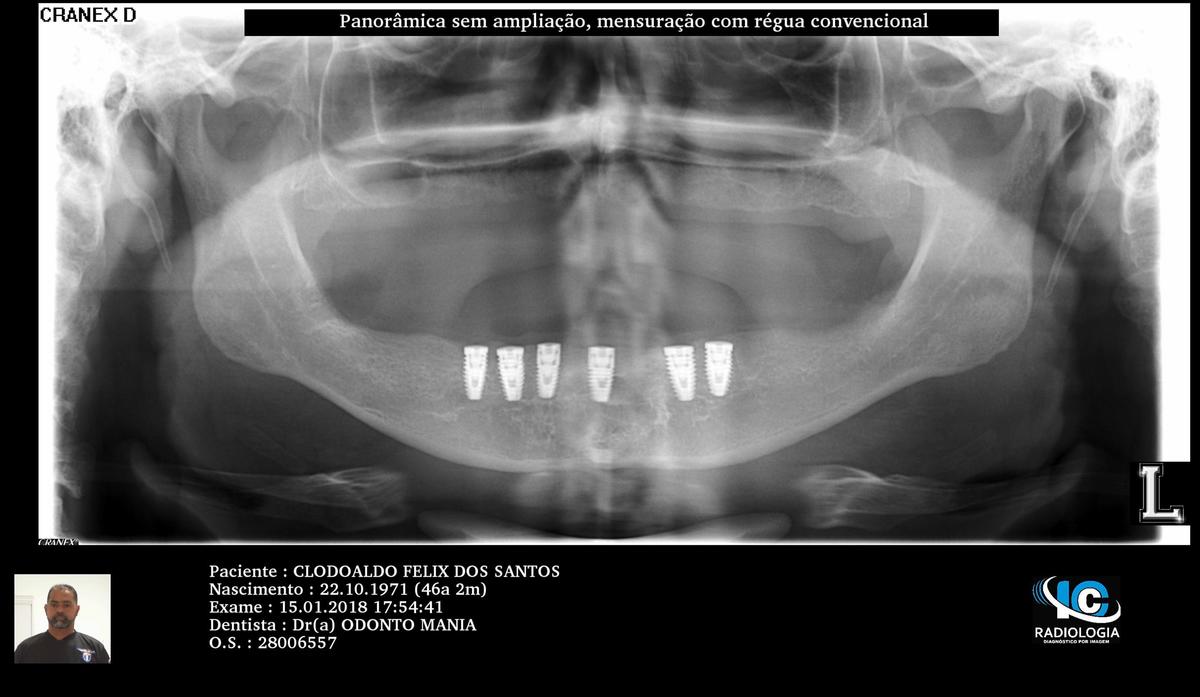

PRÓTESE TOTAL FIXA EM IMPLANTES

C.F.S.